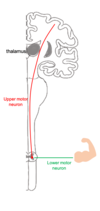

describe basic pathway of descending tracts: first order and second order neurons

first order neuron: (aka upper motor neuron): brain to the spinal cord or brainstem.It will synapse with the second order neuron,

second order neuron (aka lower motor neuron): spinal cord –> skelatal muscle